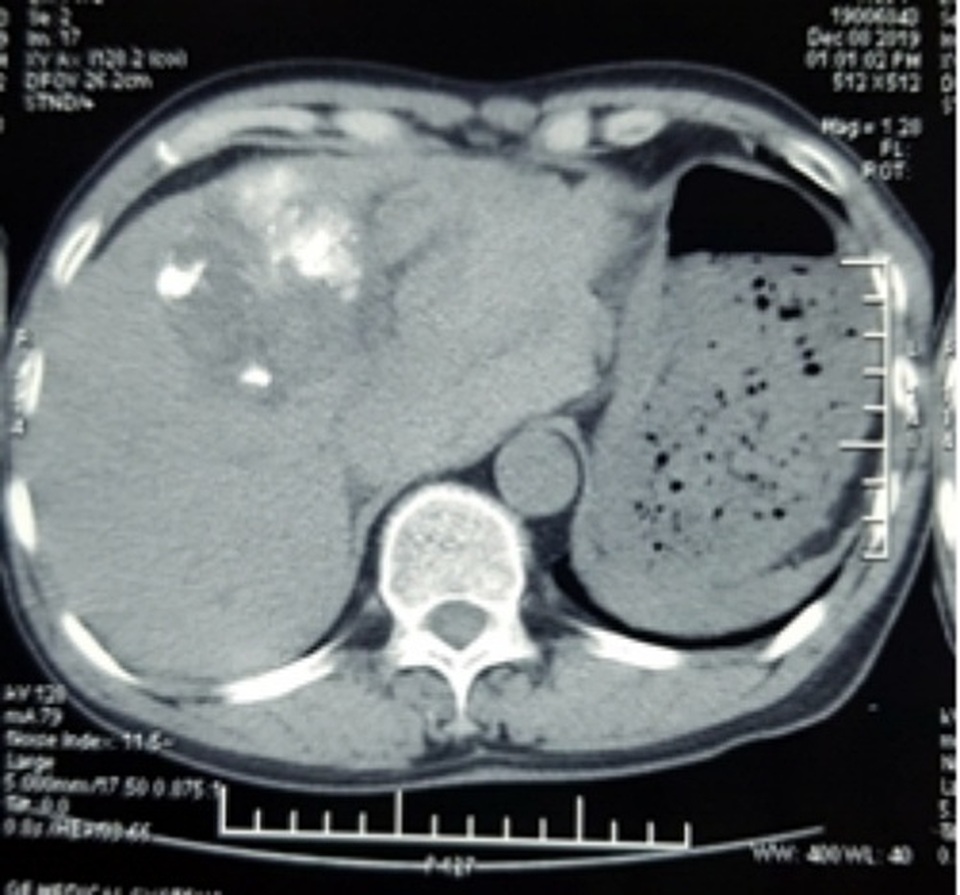

Qua siêu âm, các bác sĩ phát hiện có nhiều máu trong ổ bụng bệnh nhân. Kết quả chụp cắt lớp vi tính cho thấy, khối u gan kích thước hơn 6cm thâm nhiễm nhu mô gan trái đã vỡ, đang có dấu hiệu chảy máu, tạo khối máu tụ lớn khoang hậu cung mạc nối, nhiều dịch máu quanh gan và tiểu khung, chỗ dày nhất 6cm. Bệnh nhân được chẩn đoán sốc mất máu do u gan vỡ, nguy cơ tử vong cao.

Sau 1 tuần, kết quả chụp cắt lớp vi tính cho thấy động mạch gan trái và phải tắc hoàn toàn, khối u không còn tăng sinh mạch, không còn dấu hiệu chảy máu ra ngoài khối u. Lượng máu tụ trong ổ bụng đã giảm 50%.